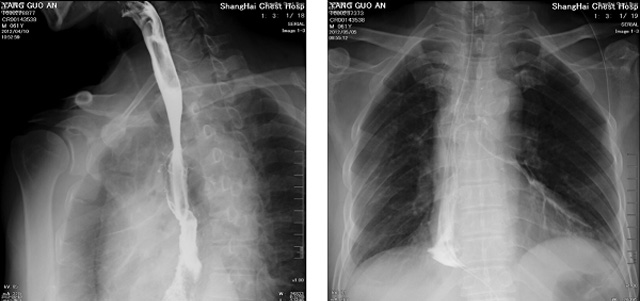

DR設(shè)備在2020年的新冠疫情中,加速了市場調(diào)整。以醫(yī)院為主的向二三級市場轉(zhuǎn)變。特別是小巧靈活的移動DR設(shè)計(jì),填補(bǔ)CT和磁共振不能三維檢查的缺點(diǎn),滿足內(nèi)科外科特別是骨科的影像診斷需求。還有懸吊DR設(shè)備CT斷層射線系統(tǒng)。使用錐束成像技術(shù)對整個(gè)脊柱和整個(gè)下肢進(jìn)行了體積三維掃描。無需使用對比劑,即可使用X射線呼吸功能標(biāo)測來模擬模擬氣流和血流,以評估患者的肺動脈血栓。

數(shù)字化X線攝影依然是患者初篩的關(guān)鍵一環(huán)。靜態(tài)DR限制于探測器平臺。只能進(jìn)行簡單普通的數(shù)字化影像檢查。胸部的疾病沒辦法篩查出微小的病灶。這樣導(dǎo)致DR慢慢的被CT跟磁共振代替。這樣造成了原來配套的數(shù)字化影像DR設(shè)備的 閑置。所以DR需要跟CT融合擴(kuò)大DR的檢查使用場景。為DR提高更多的市場價(jià)值。X射線技術(shù)的原始形式和面向未來的可能性打破了CT成像和DR成像掃描技術(shù)之間的限制。融合成像趨勢更加明顯,多峰成像趨勢發(fā)展更加迅速。